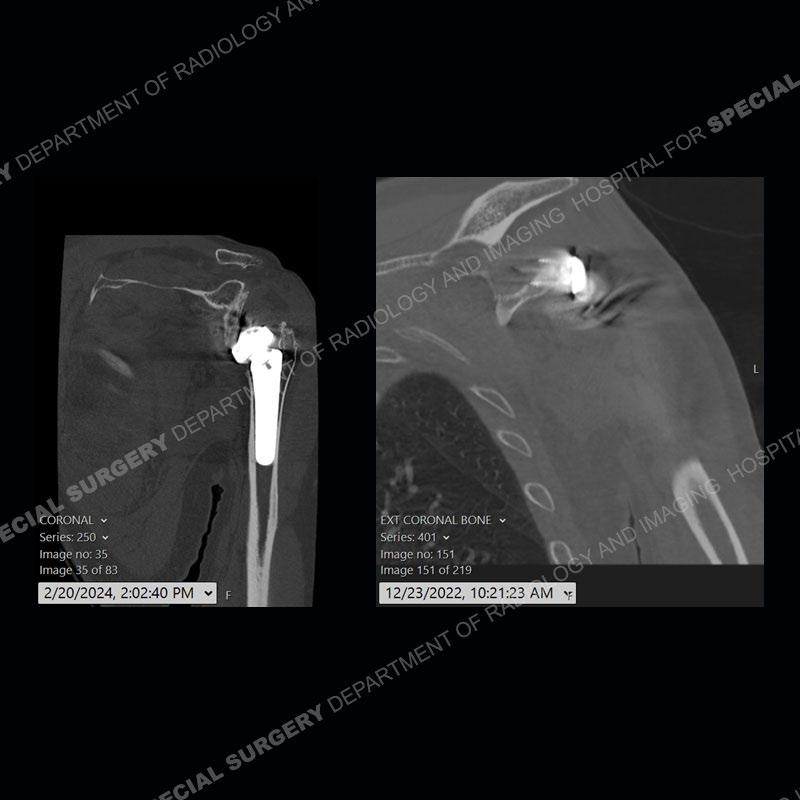

When comparing the radiographs, there is a slight change in the alignment in the components of the prosthesis. On the current radiographs, a radiolucent, crescentic focus is present at the level of the glenoid. When comparing the CT exams, there is a change at the alignment of the glenosphere and the humeral component and now a direct apposition of the components. On the current CT, the radiolucent, crescentic focus is again identified.

If comparison radiographs are present, subtle changes can be made more apparent. Instead of a space between the glenosphere and the humeral tray, there is a direct contact, and there may be an overall change in the alignment at the articulation. The displaced, radiolucent polyethylene liner depending on location can be seen on the radiographs, as in this case. At times, the liner may overlie other structures making identification very difficult on radiographs, but it should almost always be able to be identified on CT (as shown in this example as well). This patient is scheduled for revision procedure.